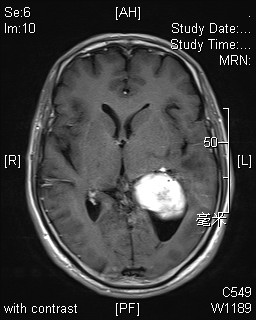

神经外科竺国充副主任医师和徐震主治医师,术前仔细研究影像学资料,分析肿瘤准确位置、大小及血供情况。考虑肿瘤位于优势半球,选择最适手术入路。2014年7月2日在麻醉科胡弘毅医师及手术室护士配合下为患者成功施行了手术。术中见肿瘤占据侧脑室三角部及体部、与丘脑及脉络丛组织粘连紧密。部分突入颞角,比邻脑干。竺国充和徐震医师在显微镜下仔细分离,历时5个小时,终于将患者脑室内肿瘤完全切除,脑脊液通路完全打通,术后复查MRI未见肿瘤信号,脑室形态恢复正常。术后病理结果为透明细胞室管膜瘤,术后患者未遗留神经功能障碍。

术前MRI 术后MRI